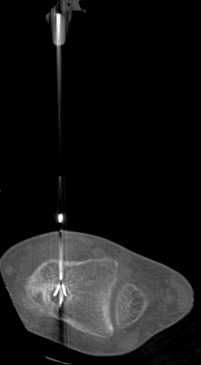

Management of Paediatric Proximal Tibia Osteosarcoma - A Novel Technique of Preservation of Physeal Growth

Osteosarcoma is a malignant tumor, the treatment of which is controversial between amputation and limb salvage surgery. Osteosarcoma occurring in a child is a challenge to manage due to the arrest of limb and the resultant limb length discrepancy. The management options for a child less than eight years of age are very limited.